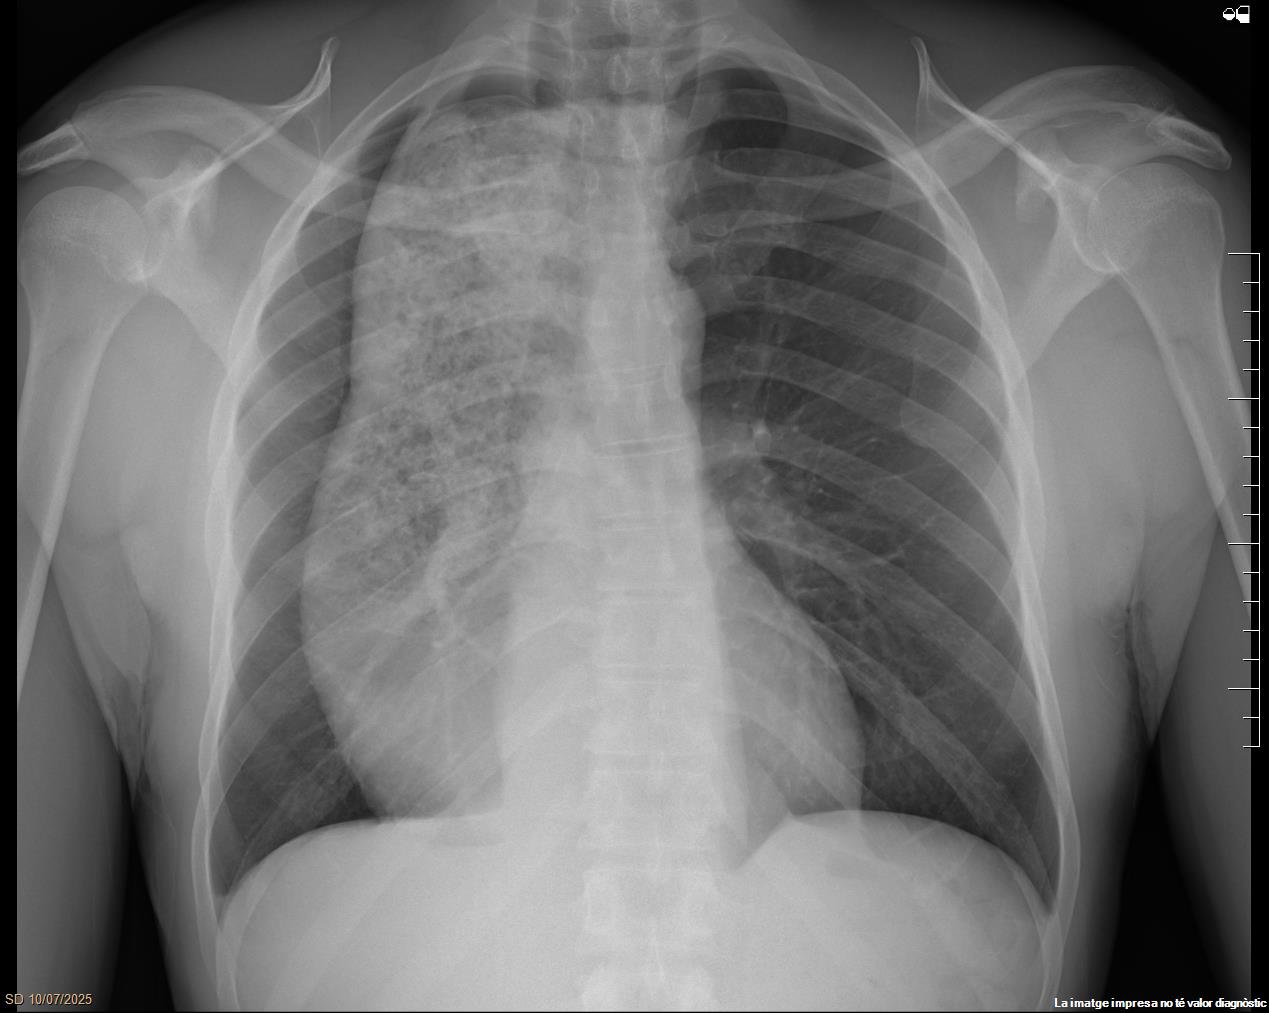

Radiografía simple de tórax (Fig. 1) que informa de gran dilatación de todo el esófago con retención de contenido alimentario, sugiriéndose la realización de un estudio de motilidad esofágica previo a descartar posible proceso neoformativo distal. Por este motivo y junto a la presencia de síndrome tóxico se solicita TC torácico con contraste (Fig. 2) que describe una importante dilatación esofágica difusa, con importante contenido de retención, adelgazamiento en punta de lápiz de la unión esofagogástrica en plano coronal, y sin claras masas ni tumoraciones, hallazgos compatibles con la posibilidad de una acalasia. También se visualiza una atelectasia laminar de aspecto reactivo a nivel del lóbulo inferior derecho, en relación con la impronta mediastínica secundaria a la dilatación esofágica descrita.